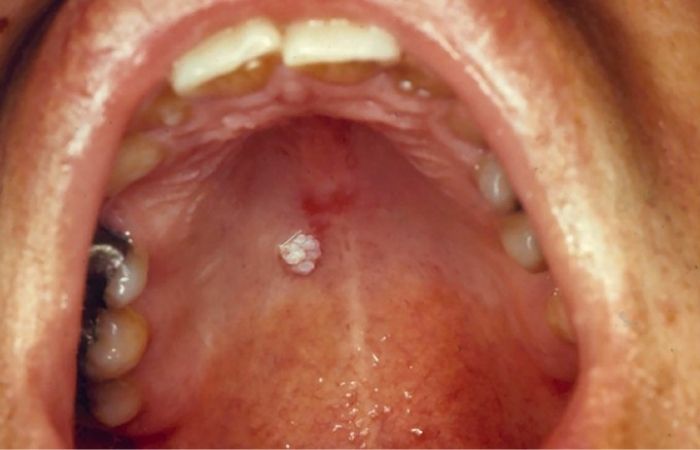

عکس زگیل سقف دهان (Palate)

سقف دهان (کام نرم یا سخت) محل بسیار شایعی برای پاپیلوماهای خوشخیم است. این ضایعات معمولاً پایهدار (Pedunculated) هستند، یعنی یک ساقه باریک دارند و یک سر شبیه به گل کلم

-عکس زگیل سقف دهان: